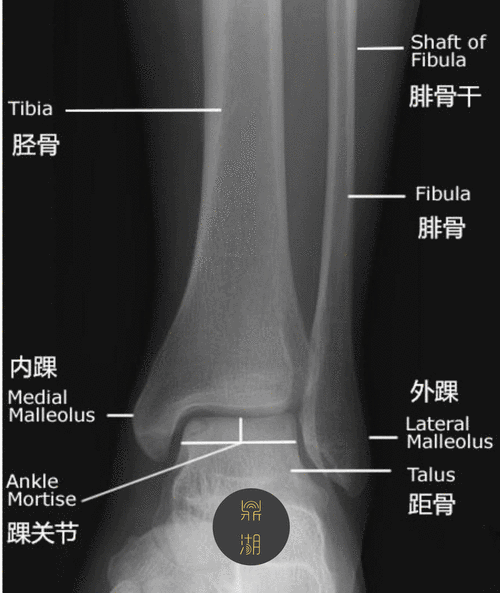

x线解剖 | 踝关节解剖

踝关节x线解剖图及常见变异.#医学影像 #医学科普 #踝关节 - 抖音

完美33张踝关节解剖高清图解

踝关节mri解剖和常见损伤类型

踝关节mri解剖及7种常见损伤类型